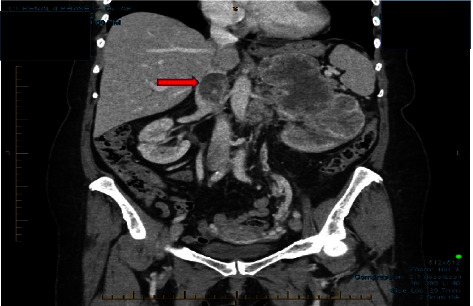

约有 4%-10% 的肾细胞癌(RCC)患者有肿瘤血管侵犯,导致肾静脉和下腔静脉(IVC)出现血栓。作者描述了一例有趣的病例,在 RCC 切除术中,IVC 肿瘤血栓移至右心腔。术中经食道超声心动图(TEE)显示右心房(RA)和右心室(RV)之间存在自由漂浮的血栓,从而做出了诊断。在完成肾切除术之前,患者需要进行紧急胸骨切开术,并使用心肺旁路术(CPB)清除心房血栓。患者完全康复并出院前往康复机构。这些发现说明了在肾切除术和输尿管血栓切除术中进行术中 TEE 监测的重要性。在该病例中,通过 TEE 诊断出了意想不到的并发症,需要及时进行心脏手术治疗。

Approximately 4%-10% of patients with renal cell carcinoma (RCC) have tumoral vascular invasion with resultant thrombi in the renal vein and in the inferior vena cava (IVC). The authors describe an interesting case of IVC tumor thrombus that migrated to the right cardiac chambers during RCC resection. The diagnosis was made by intraoperative transesophageal echocardiography (TEE), which revealed the presence of a free-floating thrombus between the right atrium (RA) and right ventricle (RV). The patient required an urgent sternotomy with cardiopulmonary bypass (CPB) for atrial thrombus removal prior to the completion of the nephrectomy. The patient made a full recovery and was discharged to a rehabilitation facility. These findings illustrate the importance of intraoperative TEE monitoring during nephrectomy and IVC thrombectomy. In this case, TEE allowed for the diagnosis of an unexpected complication necessitating prompt cardiac surgical management.